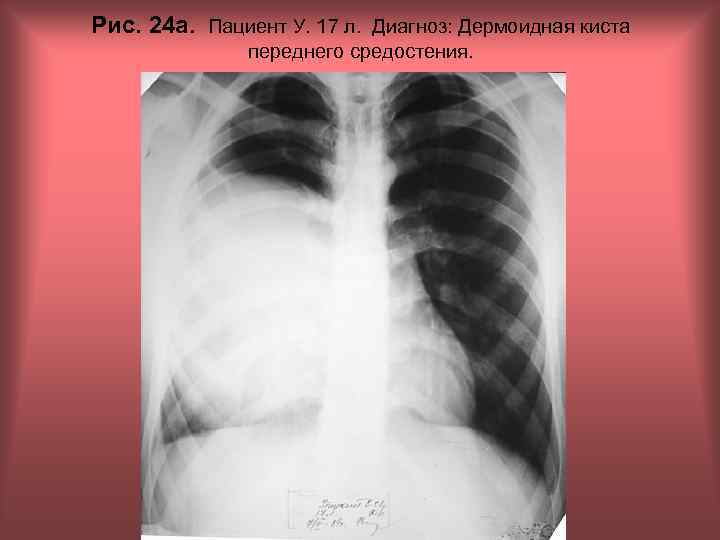

Рис. 24 а. Пациент У. 17 л. Диагноз: Дермоидная киста переднего средостения. Н. С. Воротынцева, С. С. Гольев Рентгенопульмонология